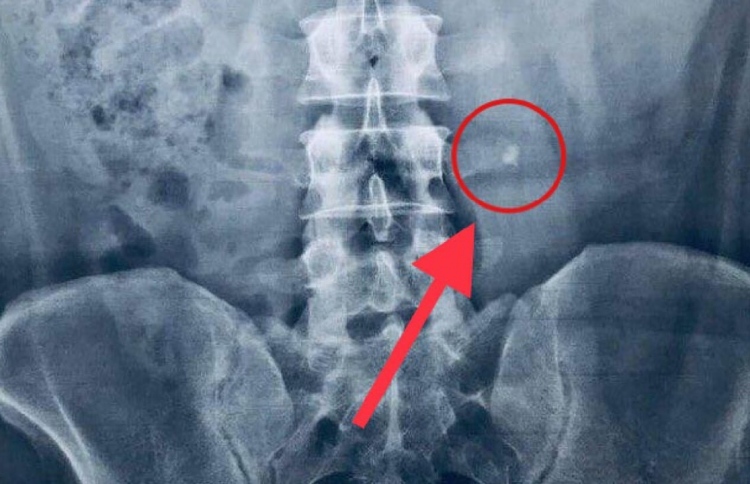

ކުރިން އަޑު ފެތުރިފައި އޮތީ، އޭނާ ގޮޅި ތެރެއަށް ވެއްޓުނީ ކަމަށެވެ. އެކަމަކު އެނގިފައިވާ ގޮތުގައި އަދީބު އައިޖީއެމްއެޗަށް ގެންދިޔައީ ޖަލު ގޮޅީގެ ފާޚާނާ ތެރޭގައި ޖެހި ނިތްކުރި ދުޅަވުމުންނެވެ.